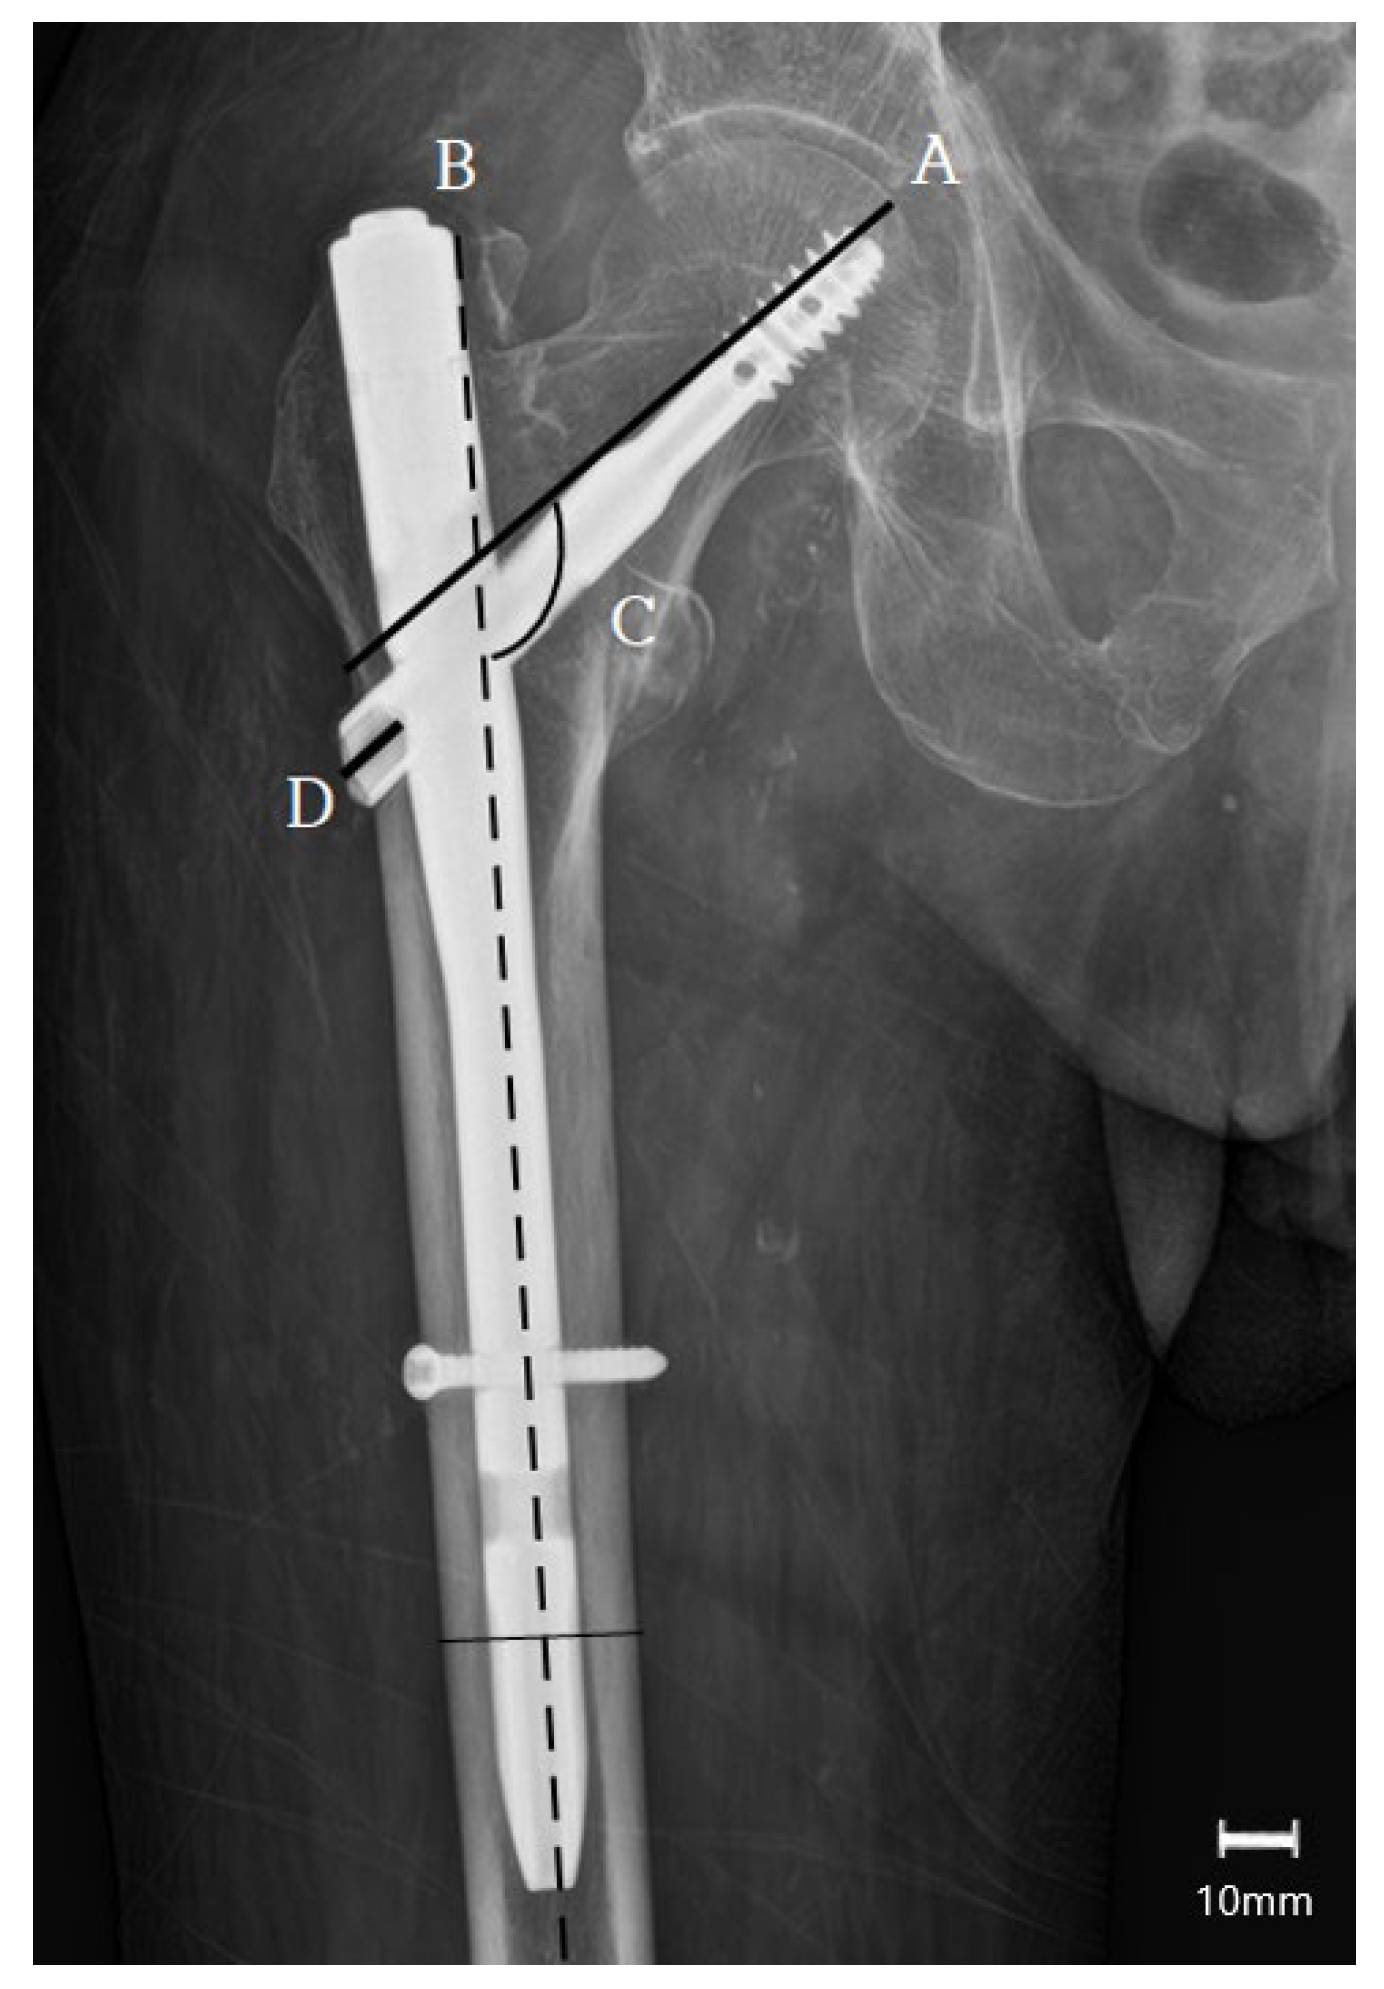

- Chinzei, N.; Hiranaka, T.; Niikura, T.; Fujishiro, T.; Hayashi, S.; Kanzaki, N.; Hashimoto, S.; Sakai, Y.; Kuroda, R.; Kurosaka, M. Accurate and Easy Measurement of Sliding Distance of Intramedullary Nail in Trochanteric Fracture. Clin. Orthop. Surg. 2015, 7, 152–157. [Google Scholar] [CrossRef] [PubMed]